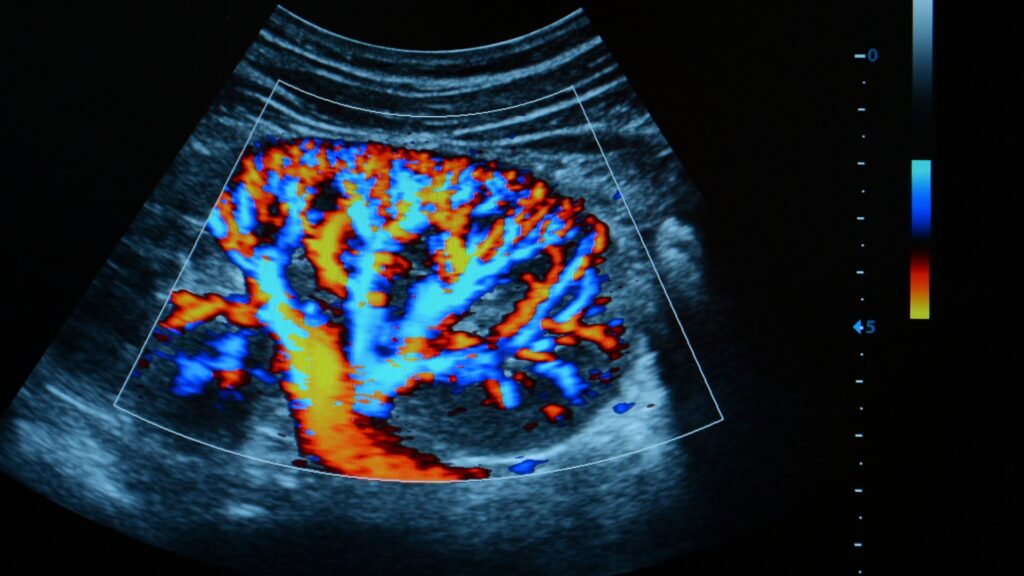

Avaliação do Fluxo Sanguíneo

Oferece dados detalhados sobre a velocidade e a direção do fluxo sanguíneo, essenciais para um diagnóstico preciso.

O paciente deita-se confortavelmente enquanto um gel condutor é aplicado na área abdominal. Um transdutor é usado para capturar imagens detalhadas das artérias, com a tecnologia Doppler colorido adicionando uma codificação de cores para facilitar a visualização do fluxo sanguíneo.